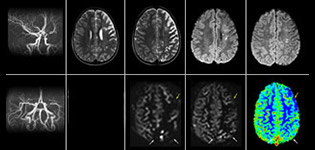

Efficiency and diagnostic confidence drive adoption of three recent imaging techniques in pediatric neuro exams at Phoenix Children’s Hospital

At PCH, fast, high resolution susceptibility weighted imaging with SWIp is now routine for traumatic brain injury imaging. Fast contrast-free perfusion imaging with pCASL is used in all patients with acute cerebrovascular accidents or abnormalities such as acute stroke. The excellent fat suppression of mDIXON TSE has become the standard at PCH for fat suppression in the spine and extremities, for imaging lesions in the soft tissues of face and neck, and for contrast enhancing abnormalities that are mostly visible with fat suppression.